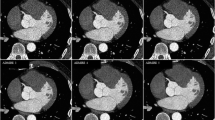

The actual measured profile curves were obtained by setting the square region of interest (ROI) across the CT images at the same position in all three image data sets, reconstructed with FBP, AIDR3D, and FIRST from the 30 patients (Fig. 1a). We placed the square ROI on the main trunk, superficial branch, and deep branch of the cystic artery. The X-axis of the square ROI represents distance along the line and the Y-axis that is normally wider than one pixel represents the averaged pixel intensity. On the actual measured profile curve, the ΔCT number in three reconstructions was calculated using the formula as below:

where HU peak is the maximum CT number of the profile curve. In addition, we selected the higher CT number of the two curve bases as an HU background to minimalize the influence of the fat density (Fig. 1b).

a Square region of interest (ROI) was placed across CT angiograms (the main trunk, superficial branch, and deep branch of the cystic artery) at the same position in the three image data sets, reconstructed with FBP, AIDR3D, and FIRST. b On the actual measured profile curve, the ΔCT numbers in three reconstructions were calculated from the HU peak and HU background (higher curve base). c On the normalized profile curve, we measured the width of the curve one-tenth above the higher base as the full-width at tenth-maximum (FWTM) in the three reconstructions

The CT number of the peak and background of the actual measured profile curve was then taken to calculate the normalized profile curve. On the normalized profile curve, we measured the width of the curve one-tenth above the higher base as the full-width at tenth-maximum (FWTM) (Fig. 1c).

Although we calculated the effect size to evaluate the influence of FIRST for the peripheral branches (the superficial branch or the deep branch) and the main trunk of the cystic artery, the superiority of FIRST for the peripheral branches was not shown (Cohen’s d effect size). Figure 3 shows a practical case of profile curves with FBP (a), AIDR3D (b), and FIRST (c) in a 67-year-old man. Figure 3d shows the ΔCT numbers of a main trunk of the cystic artery on an actual measure profile curve. The ΔCT number with FIRST is the highest (FIRST 200.00 HU, FBP 161.67 HU, AIDR3D 159.00 HU).

This figure is a Practical case of profile curves with FBP (a), AIDR3D (b), and FIRST (c) in a 67-year-old man. The square ROI was placed on all three image data sets. Axial CT image with FIRST (c) allows the best visualization of the cystic artery compared to FBP (a) and AIDR3D (b). d ΔCT numbers of a main trunk of the cystic artery on an actual measure profile curve. The ΔCT number with FIRST is the highest (FIRST 200.00 HU, FBP 161.67 HU, AIDR3D 159.00 HU). e FWTMs of main trunk of the cystic artery on a normalized profile curve. The FWTM of FIRST that represents the vessel blurring is the smallest (FIRST 2.86, FBP 3.05, AIDR3D 3.07)

The FWTM of FIRST in all the areas of the cystic artery was the smallest (Table 2): the FWTM of the main trunk; FBP 2.90 ± 1.04, AIDR3D 2.91 ± 1.03, FIRST 2.87 ± 1.02, the FWTM of the superficial branch; FBP 2.23 ± 0.60, AIDR3D 2.25 ± 0.61, FIRST 2.21 ± 0.58, the FWTM of the deep branch; FBP 2.38 ± 0.77, AIDR3D 2.38 ± 0.78, FIRST 2.31 ± 0.72, respectively. Although it has been considered that the high vessel sharpness and low blurring in FIRST reflected this result, there was no significant difference when compared with other reconstructions. Figure 3e shows the FWTMs of main trunk of the cystic artery on a normalized profile curve. The FWTM of FIRST that represents the vessel blurring is the smallest (FIRST 2.86, FBP 3.05, AIDR3D 3.07).